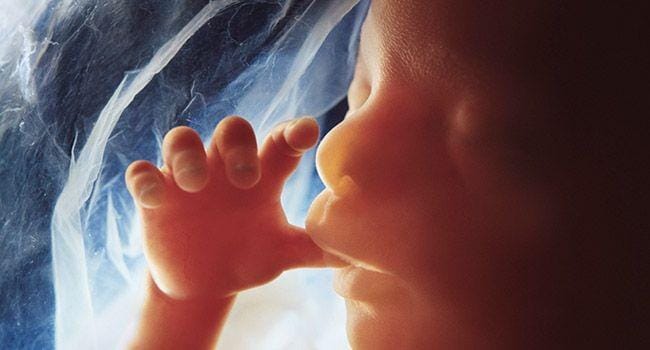

Di tahap ini organ mulai bekerja bersama dan fetus pun bisa melakukan gerakan sederhana. Misalnya menendang, menggerakkan otot wajah, dan bahkan mengisap jempol. Satu hal yang masih kurang adalah telinga bagian luar. Fetus memang sudah bisa mendengar, tetapi bentuk telinga baru muncul di usia 13 hingga 16 minggu.

14. Sidik jari

Ternyata sidik jari sudah terbentuk saat kita berada di dalam rahim ibu. Jari kaki dan tangan kita sudah terbentuk dengan sempurna di usia kehamilan 21 minggu. Untuk melengkapinya, akan muncul tekstur di permukaannya, itulah sidik jari.

15. Paru-paru

Sudah mendekati akhir dari tahap pertumbuhan. Paru-paru adalah organ terakhir yang berkembang dengan sempurna. Alasannya, organ tersebut sebenarnya tidak terlalu penting untuk fetus yang bernapas dalam cairan ketuban.